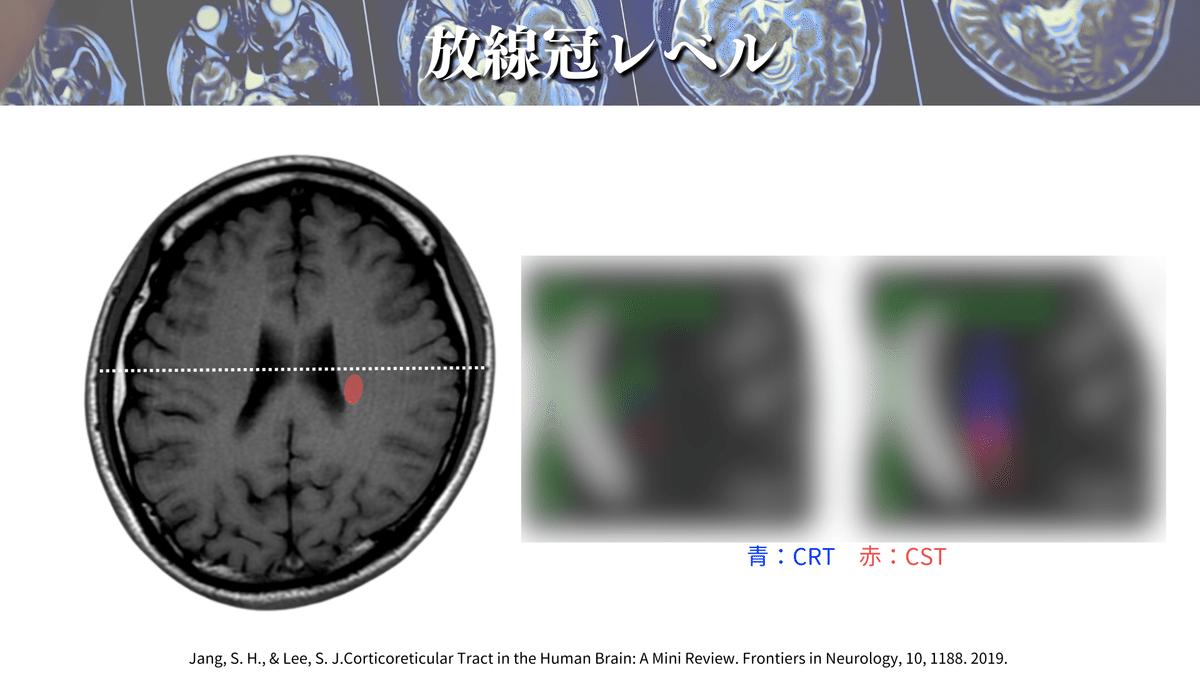

さらに解像度を上げると、、、🔍

こんな感じになります😳

やっぱり真ん中の線よりも下側にありそうですよね🤔

放線冠レベルの解説をしている論文は他にも多くあるので、オススメを紹介していきます✨

側脳室の前角や後角、側脳室の壁や島の縁などの距離から、口顔や上下肢のCSTの位置を計算する方法があります☝️

これによると、最も前外側に位置するのが口顔の線維であり、最も後内方に位置するのが下肢の線維ということが一目でわかりますね😳

これらのことから、大体この辺りを通るのかなということがわかったのではないでしょうか?🕵️(上図)